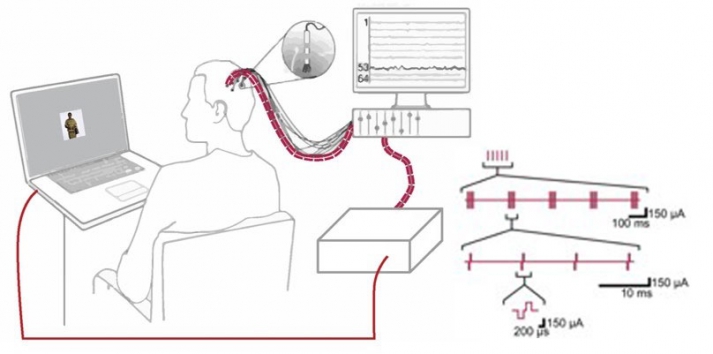

With intracranial electrodes, we can not only record the brain’s electrophysiological activity at neuronlevel spatial resolution, but we can also modulate this activity via electrical deep-brain stimulation (DBS). Because we combine iEEG recordings and DBS with cognitive tasks (e.g. mnemonic discrimination tasks), we can infer links between brain activity and human memory. Electrical stimulation is delivered through either the macro- or microelectrodes in specific temporal patterns, mimicking physiological activation.

In order to pinpoint cause and effect between specific electrophysiological patterns and cognition, we deploy closed-loop technologies. During closed-loop experiments, a real-time hardware-software system ensures that DBS is precisely timed to the occurrence of specific short-lasting (~40-1000 ms) electrophysiological patterns, such as fast oscillations (~80-120 Hz), bursts of firing neurons or phases of an underlying rhythm (e.g. theta at ~4-8 Hz). For this purpose, we take advantage of Falcon, a software platform for closed-loop experiments, which can deliver a stimulation to brain with submillisecond round-trip latency and can adapt to a variety of experiments.

6. © Mankin et al., 2021, © Titiz et al., 2017. The large image on the left was created by Mankin et al., 2021. Mankin, Emily A., Zahra M. Aghajan, Peter Schuette, Michelle E. Tran, Natalia Tchemodanov, Ali Titiz, Güldamla Kalender, et al. 2021. “Stimulation of the Right Entorhinal White Matter Enhances Visual Memory Encoding in Humans.” Brain Stimulation 14 (1): 131–40. https://doi.org/10.1016/j.brs.2020.11.015. The smaller image on the right was created by Titiz et al., 2017. Titiz, Ali S, Michael R H Hill, Emily A Mankin, Zahra M Aghajan, Dawn Eliashiv, Natalia Tchemodanov, Uri Maoz, et al. 2017. “Theta-Burst Microstimulation in the Human Entorhinal Area Improves Memory Specificity.” Edited by Inna Slutsky. eLife 6 (October):e29515. https://doi.org/10.7554/eLife.29515. Both images are reproduced according to the terms of Creative Commons Attribution License.

7. © Ciliberti & Kloosterman, 2017. Ciliberti, Davide, and Fabian Kloosterman. 2017. Reproduced according to the terms of Creative Commons Attribution License. “Falcon: A Highly Flexible Open-Source Software for Closed-Loop Neuroscience.” Journal of Neural Engineering 14 (4): 045004. https://doi.org/10.1088/1741-2552/aa7526.